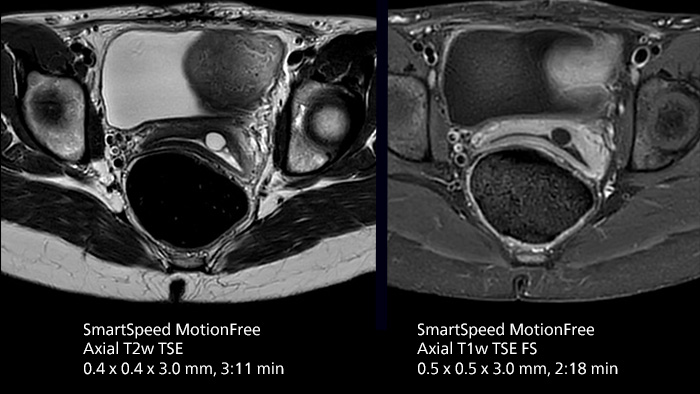

After using Philips SENSE, Mermaid Beach had adopted Compressed SENSE that offers a k-space sampling approach to speed scans while preserving details. “And now SmartSpeed enables denoising the sparse under-sampling in a new way that has allowed us to increase acceleration and bring image quality to a whole new level,” notes Kennedy, “It’s truly revolutionized our MRI work space, especially for difficult patients.”

Philips SmartSpeed has multiple approaches to denoising. Raw k-space data, coil sensitivity and coarse background information are all used and reconstructed with artificial intelligence (AI) to provide true resolution in shorter scan times1 with more sequences. Kennedy states, “I noticed that since the introduction of SmartSpeed, our day is a lot less stressed. When complicated exams need extra time, we just get on with them. And if we need to do something new or extra, we have the time for it and our workflow is still a lot more efficient.”

In addition to workflow benefits, Kennedy highlights the improvement in their diagnostic confidence. “The quality of output is so much higher than what we believed was possible, and it is very consistent across multiple patients. SmartSpeed made it feasible for us to include extra sequences in our exams and still maintain routine scanning times. This allows us to make a surprising number of diagnoses that we couldn’t have appreciated before with our previous protocol. We’ve gotten an extremely positive response from our referrers.”

“We use SmartSpeed frequently on difficult areas such as the abdomen and chest where it is common to see respiratory motion and other bowel motion,” says Kennedy. In MSK scans they use SmartSpeed not only for speeding up their exams, but also to reduce slice thickness and improve resolution “We may be increasing the number of slices, but we’re still doing this in less time than we were previously.”